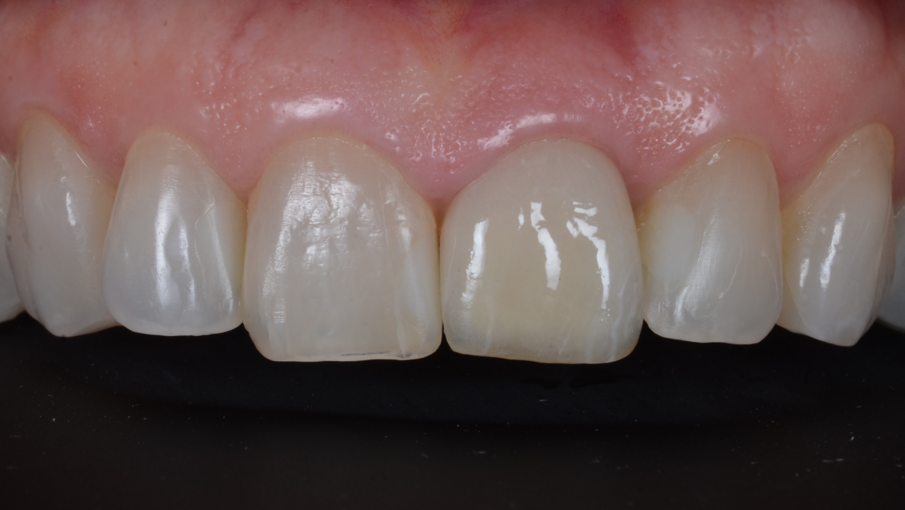

La protesi finale è stata progettata utilizzando Straumann CARES Visual con un workflow digitale. Durante la fase di progettazione è stato possibile vedere che il foro di accesso della vite sarebbe rimasto completamente sul lato palatale senza alcuna interferenza con l’estetica del restauro. Una corona monolitica in ceramica (Prettau Zirconia, Zirkonzahn) è stata fresata e cementata fuori dalla bocca su un’ampia base regolare Variobase (Straumann) con un’altezza gengivale di 1,5 mm, corrispondente al rimodellamento terapeutico dell’architettura ossea (Fig. 30). Dopo il controllo dell’occlusione, dei punti di contatto e dei movimenti di escursione, il restauro è stato inserito e avvitato con un torque di serraggio 25 Ncm (Figg. 31–33).

Fig. 31_Risultato finale del sorriso.

Fig. 32_Risultato finale da vicino.

La paziente era infermiera odontoiatrica in uno studio dentistico e quindi interagiva direttamente con molti pazienti durante i suoi turni di lavoro. Per lei è stato molto gratificante poter lasciare la poltrona sapendo che il dente compromesso era stato estratto e che l’impianto era stato posizionato e immediatamente protesizzato. La corona finale corrispondeva alla struttura e alla tonalità dei denti adiacenti, dando armonia al sorriso. Il paziente valutava la corona finale come “la ciliegina sulla torta”.